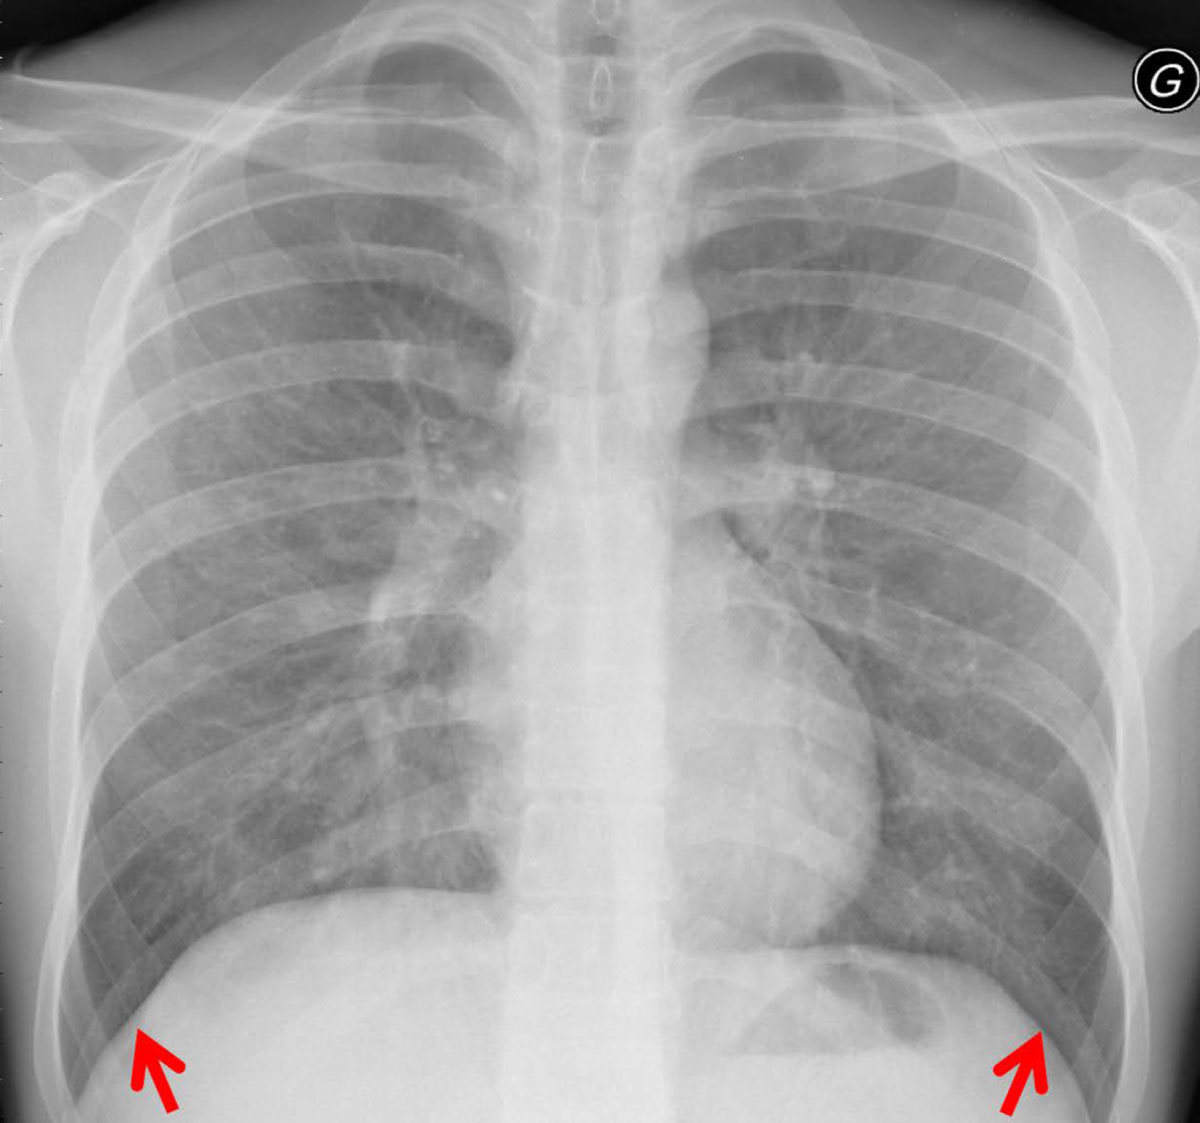

The patterns for each chest radiograph were recorded (table 3). Overall, there were no differences in patterns between the two cohorts according to the Bonferroni corrected results. However, the results from the logistic regression model showed that there was a significantly higher prevalence of reticulation in RTRs as compared with HIV patients (95.7 ± 4.2% vs 86.0 ± 4.5%; table 3). Consolidations and solid nodules were found in 47.8 ± 10.2% and 4.3 ± 4.2% of RTRs, respectively. Consolidation and multiple nodules were more prevalent in the HIV-positive patient cohort (fig. 4). For the pattern distribution within the lung lobes, we found that the basal lungs, namely, middle lobe, lingula and lower lobes, were significantly more affected in HIV-positive patients (75.0 ± 5.6% vs 58.7 ± 10.1% in RTRs p = 0.021; fig. 5). In particular, the middle lobe was mainly involved in the HIV-positive cohort (64.0 ± 6.2% vs 17.4 ± 7.7% in RTRs, p = 0.006; table 3).

Figure 4 Bilateral nodular consolidation in a human immunodeficiency virus -positive patient.